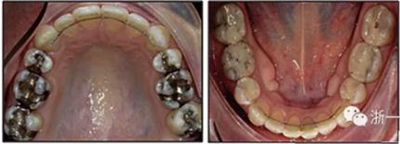

患者曾行正畸治療,現(xiàn)覺(jué)笑容不美觀前來(lái)就診。患者正面觀及側(cè)貌示下頜發(fā)育不足,偏高角,唇閉合不全。上下頜中線齊。覆合、覆蓋4毫米。磨牙關(guān)系及尖牙關(guān)系II類(lèi)。上頜擁擠度4mm,下頜擁擠度6mm。4顆第一前磨牙在第一次正畸治療時(shí)已拔除。上下牙弓呈尖圓型,牙弓狹窄。

患者側(cè)貌改善,下唇唇肌緊張消失,上下唇可自然閉合。磨牙及尖牙關(guān)系糾正至I類(lèi),覆合覆蓋正常。上下頜弓型糾正至卵圓形,牙弓寬度增加。頭影測(cè)量分析示SNA角81.8°,ANB角3°。頭影測(cè)量重疊圖示下頜骨向后旋轉(zhuǎn),垂直面高度略有增加。